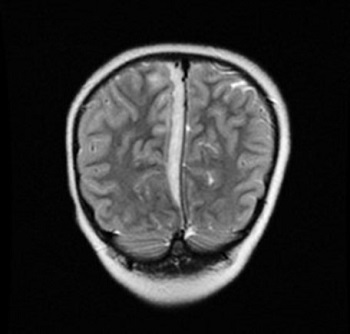

Caso 2. Niña de 10 años que ingresa por un cuadro de celulitis orbitaria acompañada de cefalea y vómitos. Se realiza una prueba de imagen que objetiva una colección intraorbitaria derecha y pansinusitis (Fig. 3). Se realiza drenaje del absceso orbitario e ingresa con tratamiento intravenoso con amoxicilina-clavulánico y ciprofloxacino ante el aislamiento en el exudado del absceso ocular de Streptococcus intermedius y en hemocultivo, de Moraxella osloensis. Ante la ausencia de mejoría clínica al cuarto día posquirúrgico, se decide realizar nueva imagen radiológica, que muestra la aparición de un empiema subdural frontal derecho (Fig. 4). Se sustituye amoxicilina-clavulánico por cefotaxima y se añade dexametasona al tratamiento. Se realiza craneotomía frontal derecha para drenar el empiema. En las muestras recogidas se aísla Streptococcus intermedius y Parvimonas micra, motivo por el que se asocia al tratamiento metronidazol intravenoso. La evolución, clínica y radiológica, es favorable tras seis semanas de tratamiento antibiótico intravenoso, y permanece asintomática al alta.

| Figura 3. Colección intraorbitaria derecha. TC de órbita: colección de 2 cm de diámetro, intraorbitaria extraconal superolateral derecha, junto a glándula lagrimal; ocupación mucosa de seno frontal, maxilar y de celdillas etmoidales derechas |